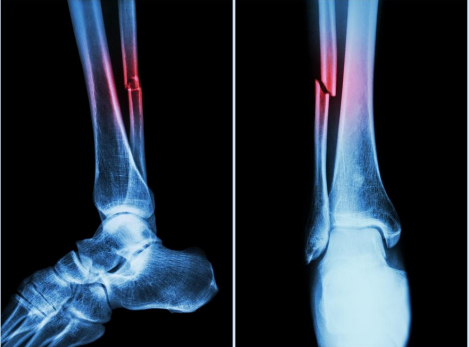

● X-rays are used to see the fracture and bone displacement.

Puwadol Jaturawutthichai. (2022). [Xray]. Fracture fibula (leg bone). X-ray of leg (2 position: side and front view). https://www.shutterstock.com/image-photo/fracture-fibula-leg-bone-xray-2-248971054